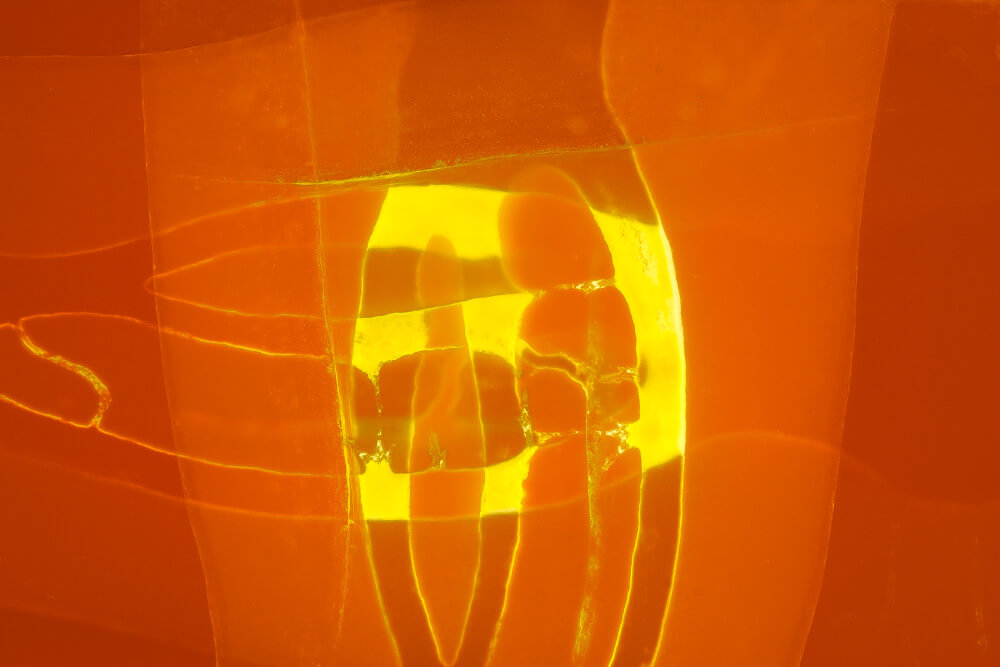

Bildauswahl für Kunstliebhaber

- Foto hinter 3mm Acrylglas, rahmenlos

- hochwertige, unsichtbare Aufhängung, "schwebend“

- Hoher UV-Schutz für lang anhaltend strahlende Farben

- Bruchsicher und leichter als Glas

- Beeindruckende Farben und brilliante Tiefenwirkung

- Druck erfolgt ohne Wasserzeichen

- Bildgröße: 60 x 90 cm, Querformat

-

Preis: 490,00 Eurozuzüglich 16,90 Euro Versand & Porto innerhalb Deutschlands, weiterer Versand auf Anfrage

Wenn Sie Interesse an den Fotos transparenter Zahnpräparate haben, bieten wir hier die Möglichkeit einige Versionen als Acrylbilder (alle Detailinformationen zu Größe und Preis siehe obige Auswahl) zu bestellen.

Die Bilder sind nicht nur zur Praxisverschönerung geeignet sondern auch eine wertvolle Unterstützung bei der Patientenberatung vor endodontischen Behandlungen.